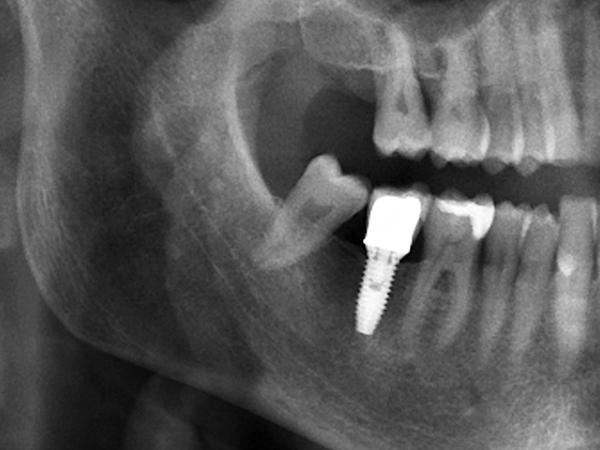

최소식립 전악임플란트는 육안이나 감에 의존하는 것이 아니라 디지털 기술을 통한 모의 수술로 안정성과 정확도를 높인 치료 방법입니다.

특히 네비게이션 임플란트는 잇몸을 절개하지 않거나 최소한으로 절개를 할 수 있기 때문에 출혈과 통증이 적고, 비교적 빠른 시간 안에 회복할 수 있다는 큰 장점을 가지고 있어 만성질환자 혹은 고령자에게도 적합한 치료방법입니다.

[임플란트] 타치과 임플란트 실패 후 재식립 사례

최소식립 전악임플란트는 칼로 잇몸을 절개하는 방법이 아닌 임플란트 식립 부분만 작은 홈으로 구멍을 뚫어 시술하는 방법입니다. 이 치료 방법은 수술 후 통증이나 붓기, 출혈이 거의 없어 부담이 없는 수술입니다.

기존의 절개 수술에 비해 수술 시간이 짧고 병원 내원 횟수가 적어 연세가 많으신 고령의 환자 또는 당뇨와 고혈압 같은 전신 질환이 있으신 분들도 안전하게 시술하실 수 있어 최고의 정확성과 안정성을 보장하며 부작용을 최소화합니다.